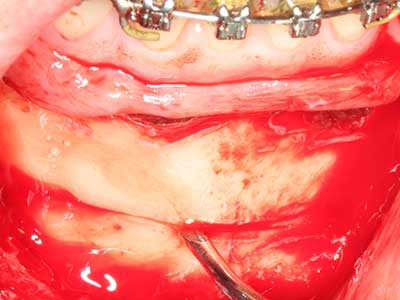

Piezo surgery has additional advantages when harvesting bone blocks. In addition to the high precision with osteotomy described above, the use of the thin saw tips specifically minimizes loss of material. Greater loss of material during harvesting can be expected with the thicker instrument tips, particularly when using Lindemann drills (Lakshmiganthan, Gokulanathan et al. 2012). The basal separation, which is necessary particularly for retromolar block transplants, is simplified by specially designed rectangular saws, with the result that piezo surgery is viewed as a precise, simple and safe procedure for harvesting retromolar bone blocks (Happe 2007) (Fig. 1-12).

Fig. 3: Basal separation of the block is easier with specially angled attachments.